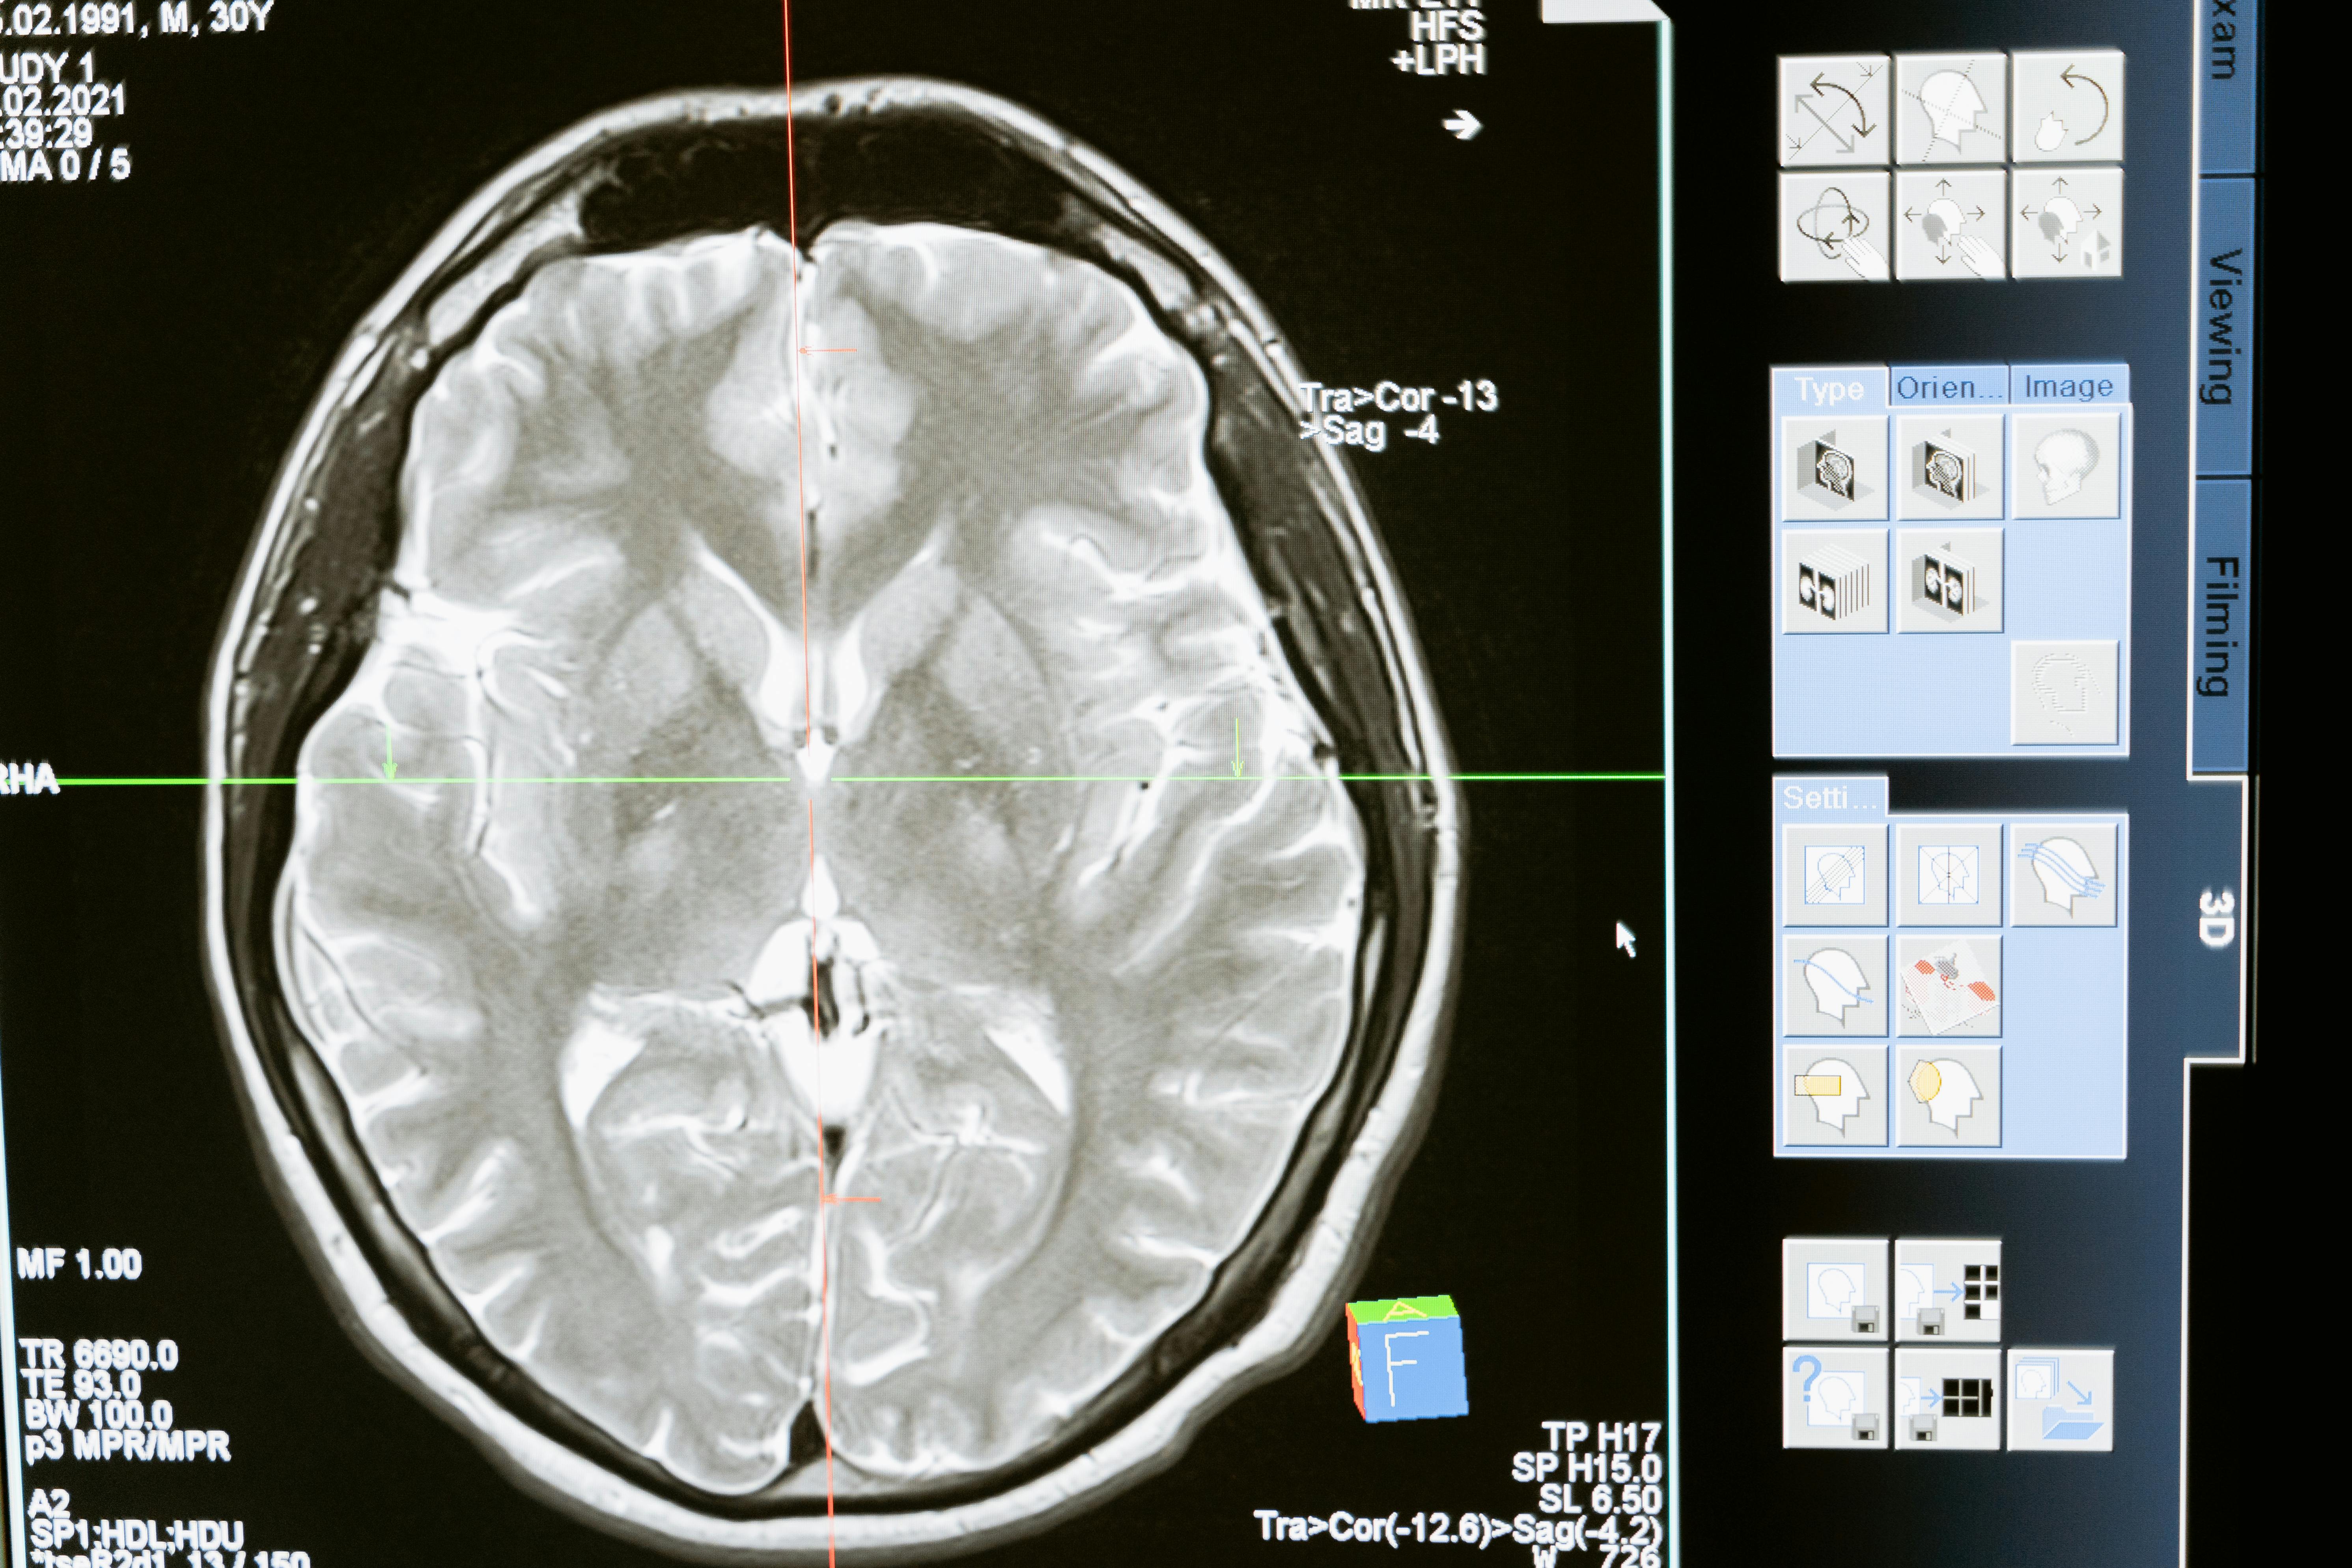

Icometrix已凭借其icobrain平台成为AI驱动神经病学诊断领域的领导者。该平台的核心是icobrain ARIA,这是首个获得FDA批准的AI驱动软件,用于检测淀粉样蛋白相关成像异常(ARIA)。ARIA是与近期推出的淀粉样蛋白靶向阿尔茨海默病药物(如Leqembi和Kisunla)相关的已知副作用。通过整合icobrain ARIA,GE医疗旨在增强其在监测接受这些新型阿尔茨海默病疗法患者的安全性和治疗效果方面的能力。此次收购还将使Icometrix的平台与GE医疗现有的MRI系统整合,并计划通过商业分销和临床整合,将icobrain ARIA的访问权限扩展到所有供应商的MRI系统。这种战略方法解决了互操作性挑战,并旨在加速AI工具在神经病学诊断中的应用。

Icometrix的技术还包括icobrain ms,该技术已证明能够减少病灶计数中的评分者内部和评分者间变异性,将检测亚临床疾病活动的敏感性提高到76%,而标准放射学读数则较低。